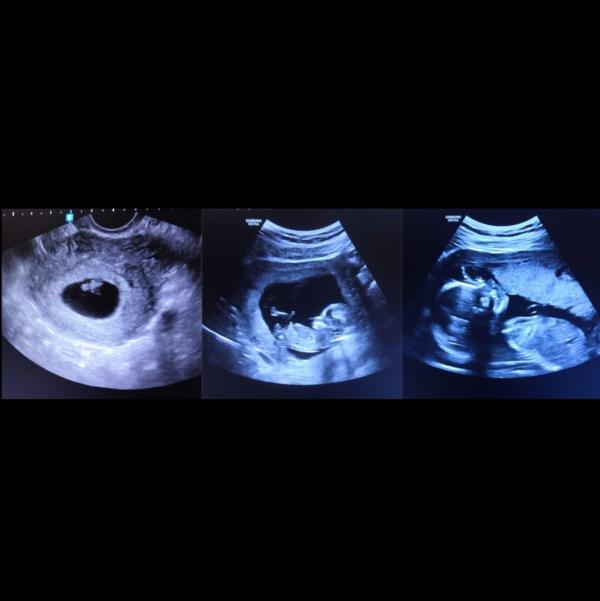

Вчера у нас был второй скрининг😊

Боже мой, как же быстро растут малыши.

Нам подтвердили нашу малышку, нашу крошку❤️🧚🏻♀️

21 неделька.